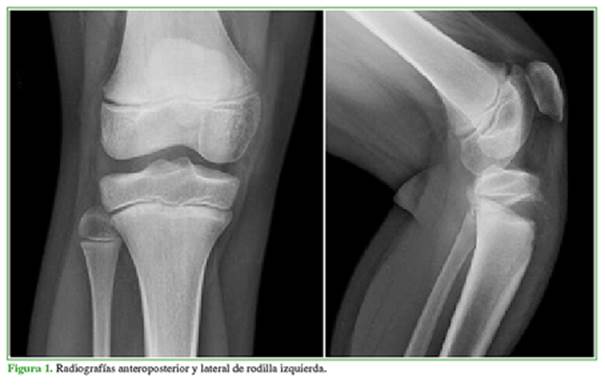

Se solicitaron radiografías anteroposterior y lateral de rodilla izquierda, en las que se apreciaba una epifisiólisis tipo I de Salter-Harris, y tipo IV-A de la clasificación de Ryu y Debenham3 (Figura 1). Tras informar al paciente y a los padres se decidió el tratamiento quirúrgico urgente. Se procedió a la reducción cerrada de la fractura y la fijación con dos agujas de Kirschner (Figura 2). No había inestabilidad en la rodilla. La evaluación detectó la presencia de pulsos distales y el examen con oxímetro de pulso también arrojó valores dentro de la normalidad. Se inmovilizó con una férula inguinopédica.

El diagnóstico inicial se basa en las radiografías anteroposterior y lateral de rodilla. Inicialmente será suficiente con estas pruebas, pero si se sospecha una epifisiólisis tipo III o IV, se debería solicitar una tomografía computarizada para valorar la extensión de la fractura e incluso una resonancia magnética para conocer el posible daño de partes blandas, como meniscos o ligamentos cruzados.